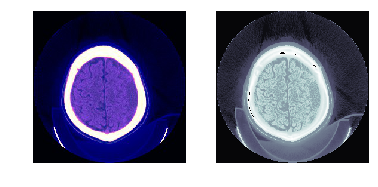

(0028, 0004) Photometric Interpretation CS: 'MONOCHROME2'

(0028, 0010) Rows US: 256

(0028, 0011) Columns US: 256

(0028, 0030) Pixel Spacing DS: [0.488281, 0.488281]

(0028, 1050) Window Center DS: "40.0"

(0028, 1051) Window Width DS: "100.0"